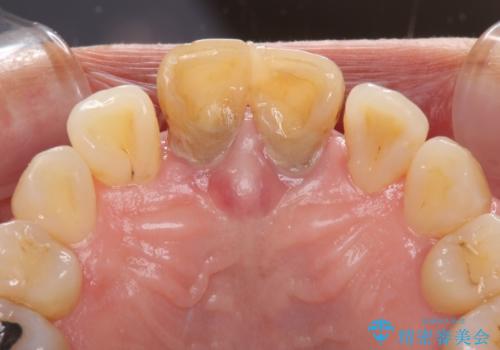

- 上の前歯の変色と、下の前歯のデコボコを気にして来院された患者様です。

前歯はオールセラミッククラウンに補綴することとしました。

当初は上顎の補綴治療のみを希望されていましたが、奥歯にブリッジなど補綴物が多くあり、前歯も変色しているため、治療費が高額となってしまうことが懸念されました。

相談の上、最も気になっている前歯の部分矯正と補綴治療により口元の改善を図ることとしました。